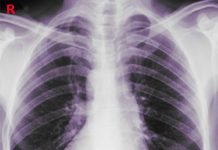

Görüntüleme

Koroner anjiyografi: Koroner arterlerde anlamlı darlık saptanmadı

Ekokardiyografi: Sol ventrikül apeksinde akinezi, bazal segmentlerde hiperkinezi

Hastada anterior duvar STEMI değil, Takotsubo kardiyomiyopatisi olduğu belirlendi.

Hastada Takotsubo kardiyomiyopatisi tanısı konuldu.

Koroner anjiyografi: Koroner arterlerde darlık saptanmadı

Hastada anterior duvar STEMI değil, Takotsubo kardiyomiyopatisi tanısı konuldu.